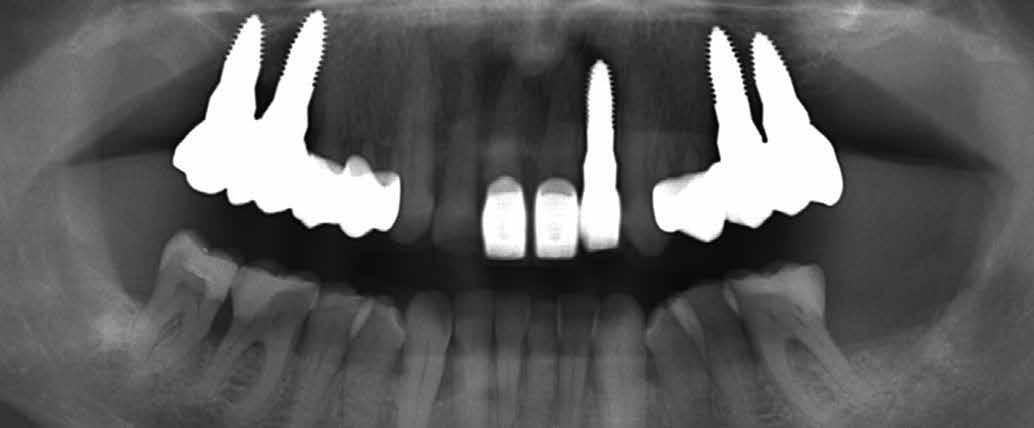

1. a–d. ábra: Műtét előtti állapot mind a négy páciensnél. 1. eset (a). 2. eset (b). 3. eset (c). 4. eset (d).

digitális implantátumtervezés követett (SICAT és Sidexis, mindkettő Dentsply Sirona; 1. ábra).

3. a–b ábra: Röntgenfelvételek három hónap után (a) és a gyógyulási csavarok behelyezve (b, 1. eset).

4. a–b ábra: Röntgenfelvételek öt hónappal később (a) és a gyógyulási csavarok behelyezve (b, 2. eset).

5. a–c ábra: Röntgenfelvételek öt hónappal később (a) és a gyógyulási csavarok behelyezve (b és c, 3. eset).

6. a–b ábra: Röntgenfelvételek öt hónappal később (a) és a gyógyulási csavarok behelyezve (b, 4. eset).